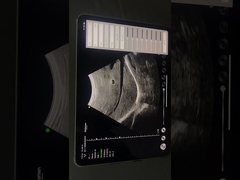

Kalite Portatif Ultrason tarayıcı, taşınabilir ultrason tarayıcı manufacturer from China